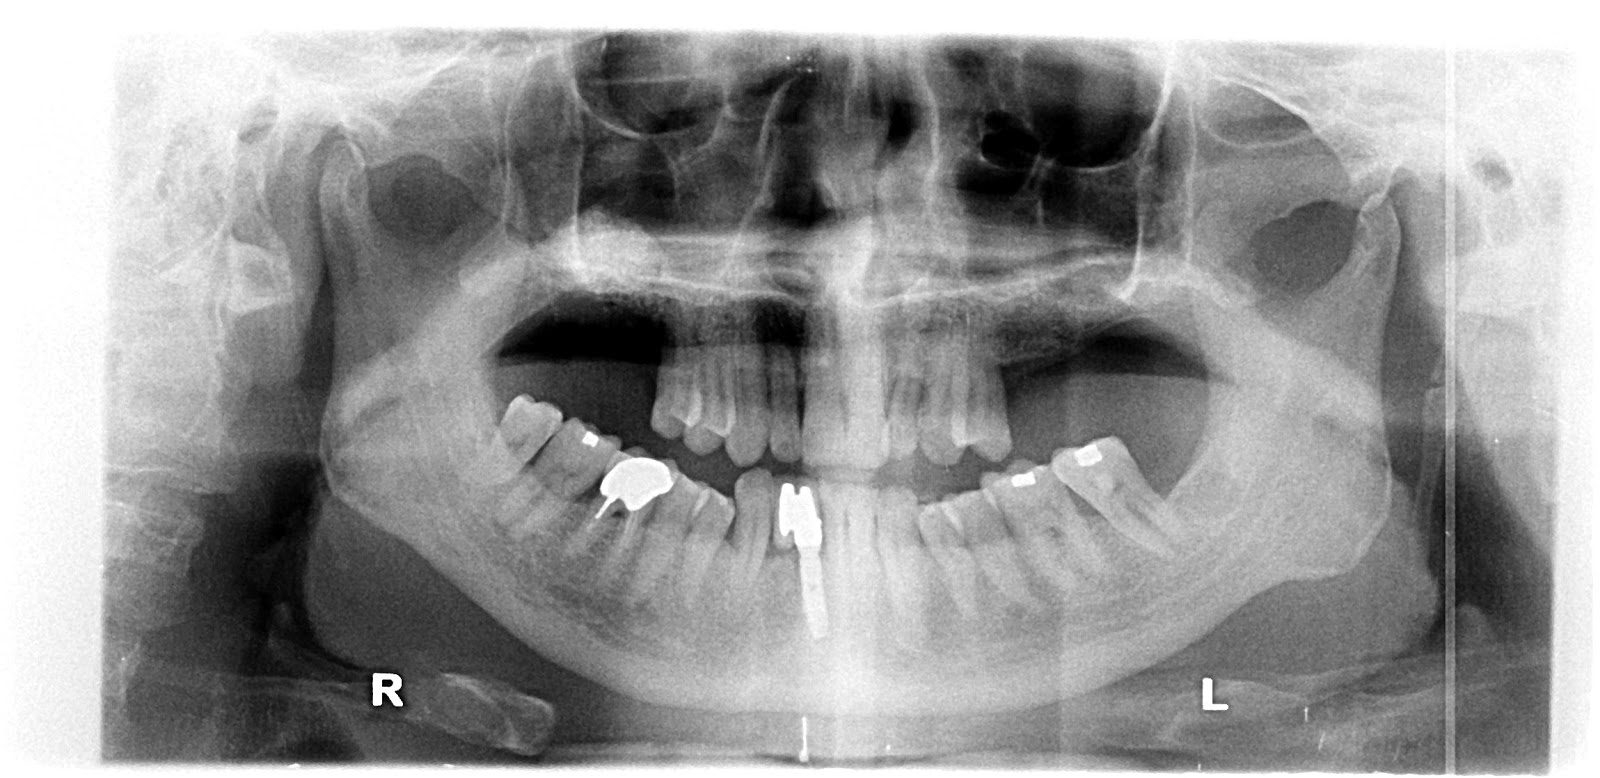

Prior to commencement of surgery, careful and detailed planning is required to identify vital structures such as the inferior alveolar nerve or the sinus, as well as the shape and dimensions of the bone to properly orient the implants for the most predictable outcome. Two-dimensional radiographs, such as orthopantomographs or periapicals are often taken prior to the surgery. Sometimes, a CT scan will also be obtained. Specialized 3D CAD/CAM computer programs may be used to plan the case.

VISTA for single upper anterior tooth + GBR

PreOP

PostOP

4 wks’ healing

6 mo healing

Post dental implantation.

Bone resorption after extraction